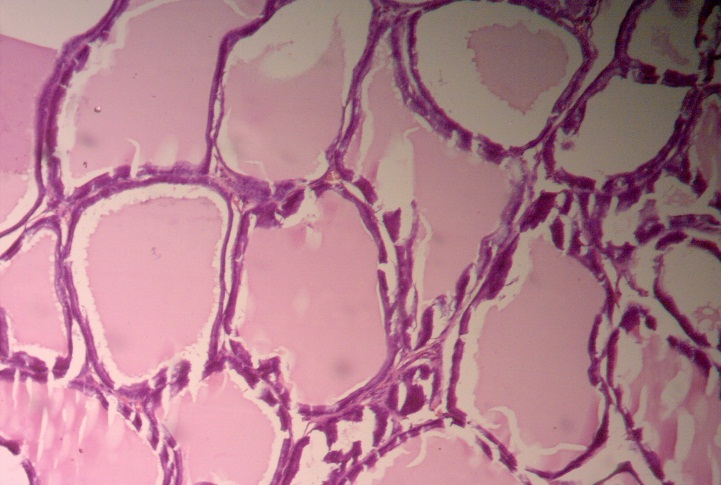

Figure 4. Normal rat seminal vesicle

The seminal vesicle of the control group rats showed complex, glandular and lumen was irregular and mucosal exhibited thin and anatomizing folds.